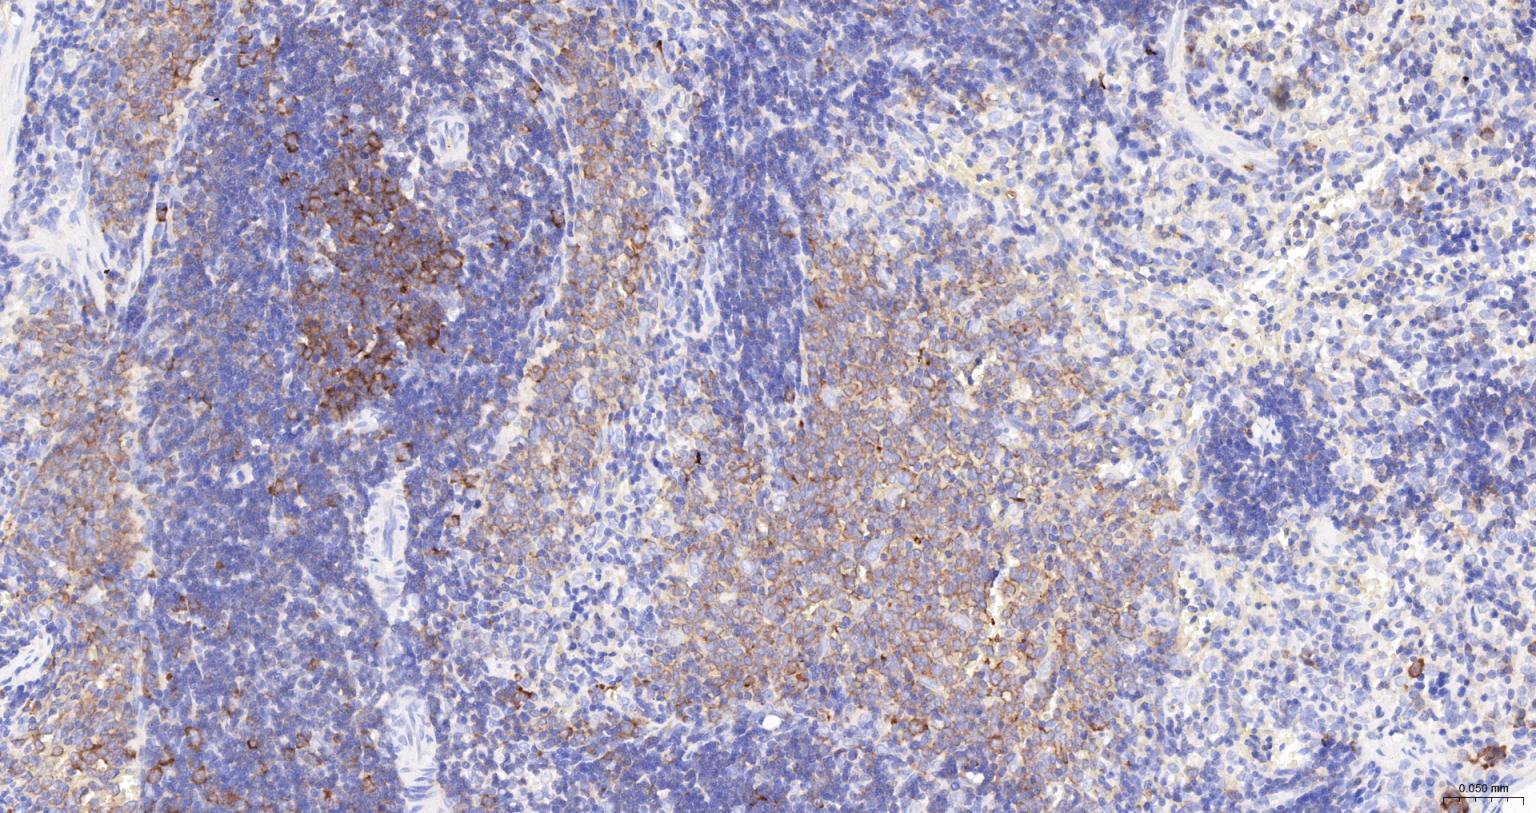

| IHC-P | Human, Mouse, Rat | 1:100-500 | |